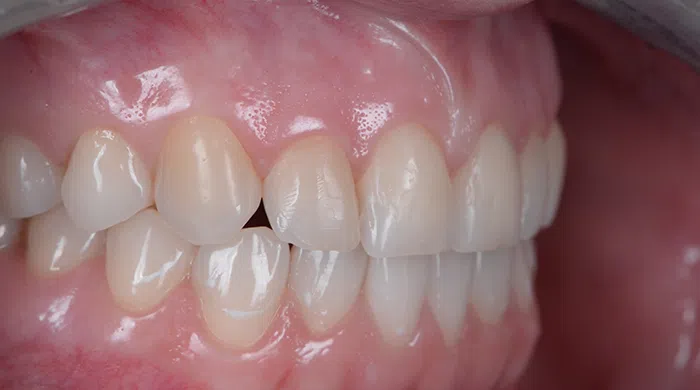

Caz de estetică dentară – Coroane ceramică presată E-Max

Provocarea acestui caz a fost tratarea minim invazivă a dinților restanți, în urma înlocuirii coroanelor vechi și obținerea unor dinți cu un volum mai mare pentru echilibrarea zâmbetului într-un aspect cat se poate de natural.

Pacientă a beneficiat de corecție gingivală cu laser pentru uniformizarea asimetriilor gingivale, tratamente endodontice de canal sub microscop, obturațiile vechi (plombe) schimbate cu materiale de compozit cu particule nanoceramice, și fațete dentare din ceramică presată E-Max.

Termen de finalizare 2 săptămâni de la amprentarea finală.